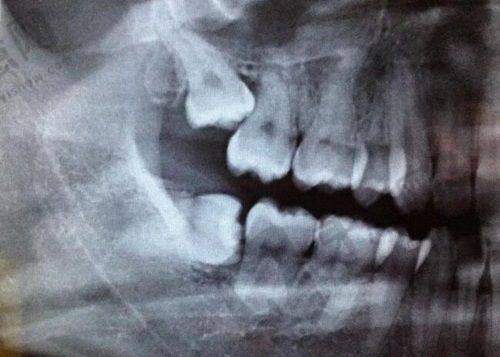

深圳二档社保参保人进行根管治疗是可以使用医疗保险报销的。根管治疗是一种治疗牙齿感染的方法,符合基本医疗保险的诊疗项目。不过,要顺利报销,得在医疗保险定点医疗机构进行治疗。

根管治疗费用也在报销范围内,前面已经提到,这对于患有牙髓炎等需要根管治疗的患者来说是个好消息。还有治疗牙周病、牙龈病的费用同样可以报销。另外,补牙(包括基本材料、治疗费)也能通过医疗保险报销。